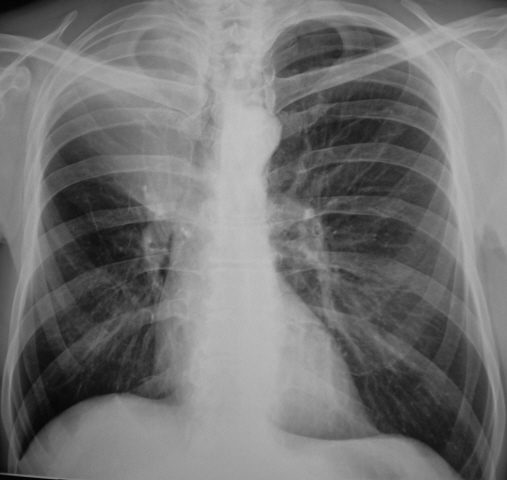

Помимо опроса и объективного осмотра, включающего перкуссию и аускультацию грудной клетки, проводят рентгенологическое исследование в двух положениях тела (в 2-х проекциях). Это основной метод обнаружения ателектазов легких.

На рентгеновских снимках выявляют следующие признаки, указывающие на спадение легочной ткани:

Однородное затемнение в области поражения. Размеры тени зависят от вида ателектаза: при долевом выявляется обширное затемнение, при сегментарном — в виде клина или треугольника, расположенного вершиной к корню легкого, дольковые ателектазы множественные и похожи на очаговую пневмонию. Дистензионный ателектаз расположен низко, около диафрагмы, имеет небольшие размеры и вид поперечных полос или темных дисков. Смещение органов: при компрессионном ателектазе смещение наблюдается в здоровую сторону, так как на стороне поражения давление больше, при обтурационном, наоборот – смещение будет в сторону ателектаза, так как на стороне поражения нарастает притягивающее отрицательное давление. Подъем купола диафрагмы – это видно по расположению печени.

Помимо всего перечисленного выше, рентгеноскопия, то есть исследование «вживую», позволяет увидеть куда смещаются органы в зависимости от фазы дыхания, кашля. Это является дополнительным признаком ателектаза, помогающим выявить тип болезни.

Предварительным, рентгенологическим диагнозом является «синдром правой доли», при котором выявляется затемнение площади средней доли правого легкого.

Частое возникновение ателектаза правого легкого связано с анатомическими особенностями правого среднедолевого бронха: он узкий и длинный, поэтому часто происходит его перекрытие при патологическом процессе.

Во время инструментальных диагностических манипуляций важно не только установить наличие ателектаза и его точную локализацию, но и уточнить объем спавшейся ткани, чтобы определить правильную тактику лечения и объем лечебных манипуляций. На рентгенограмме для диагностики ателектаза имеет значение состояние не только ткани легких, но и корней легких, ребер, органов средостения, купола диафрагмы, плевры, плевральной полости и даже позвоночника (будет наблюдаться его сколиотическое отклонение в направлении выпуклости в сторону пораженного легкого)

На рентгенограмме для диагностики ателектаза имеет значение состояние не только ткани легких, но и корней легких, ребер, органов средостения, купола диафрагмы, плевры, плевральной полости и даже позвоночника (будет наблюдаться его сколиотическое отклонение в направлении выпуклости в сторону пораженного легкого).